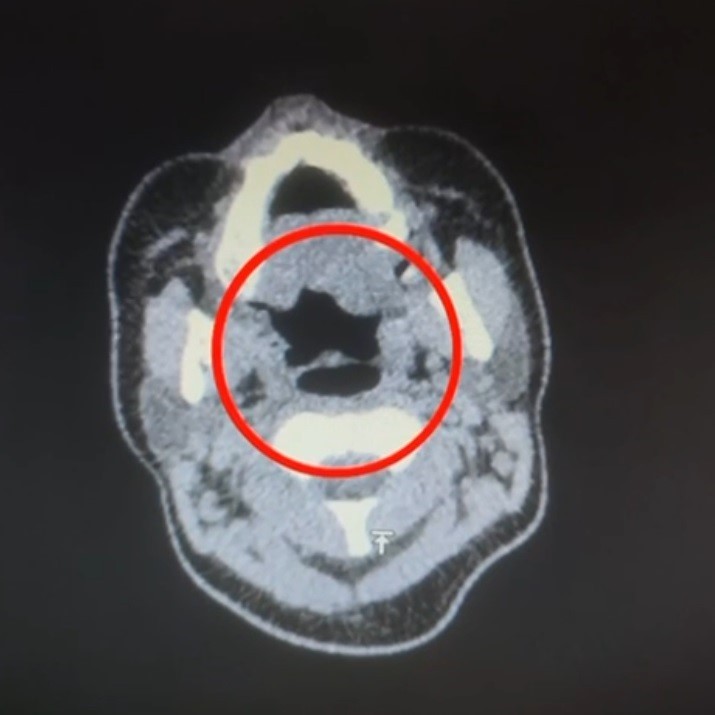

Şüphelinin yapılan iç beden muayenesinde, mide bölümünde tespit edilen 50 adet kapsül halinde toplam 500 gram uyuşturucu madde ele geçirildi.